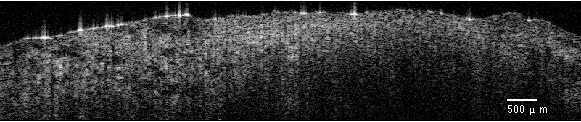

Typical OCT images of normal and tumor tissue types are shown in Figure 2. The OCT image was cropped to 1.5 mm (horizontal) ×\times 0.75 mm (axial) to show the tissue part of the image. A clear structural difference can be observed between the adipose tissue and the tumorous tissue: As the adipose tissue is composed of relatively large cells, a kind of periodicity is observed in the related images. The images of timorous tissue have less clear spatial structure.

(a) OCT image of adipose tissue

(b) OCT image of tumorous tissue

Figure 2: Breast OCT images.